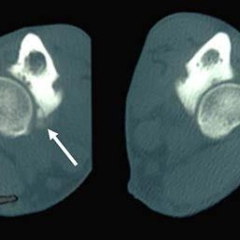

- For elbow dysplasia, there is a category of normal, or unaffected, and three categories of worsening elbow dysplasia as evidenced by increasing severity of radiographic osteoarthritis.

- Further details on the breeds and the scoring criterion can be found in this published paper. A new manuscript is in preparation. Images of dogs with good and poor (dysplastic) hip conformation and also a tomographic slice through the elbow of a dog with fragmented medial coronoid process (part of the elbow dysplasia syndrome) can be seen below.